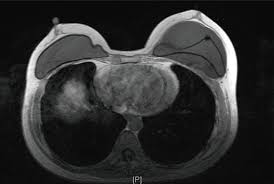

If you have silicone breast implants and suspect that an implant might have ruptured, talk to your plastic surgeon. When a rupture occurs your breast (s) will immediately deflate, usually within a day or two, and breast size will noticeably change. Nevertheless, your body will try to contain any silicone gel seeping in your breast tissue by forming a scar tissue around it, called "granulomas" or "siliconoma". Rupture can also cause capsular contracture. The relationship of free silicone to development or progression of disease is unknown. With silicone gel implants, you aren't able to physically see the appearance of a ruptured implant, whereas with saline implants, you will see a deflated breast with implant rupture. An imaging test, such as an mri or ultrasound, can show whether the implant has ruptured. What are the dangers of silicon? What is the life expectancy of silicone breast implants? Apr 01, 2019 · however, some may remain around the ruptured implant, and this can cause the fluid to change color. What are the risks of silicone implants? Silicone implant rupture that doesn't cause any noticeable symptoms is known as "silent rupture.". This makes is much more difficult to detect a rupture.

Aug 20, 2020 · pain, soreness or swelling. This makes is much more difficult to detect a rupture. If you have silicone breast implants and suspect that an implant might have ruptured, talk to your plastic surgeon. Nevertheless, your body will try to contain any silicone gel seeping in your breast tissue by forming a scar tissue around it, called "granulomas" or "siliconoma". An imaging test, such as an mri or ultrasound, can show whether the implant has ruptured. Changes in size or shape. What are the risks of silicone implants? What are the dangers of silicon? Silicone implant rupture that doesn't cause any noticeable symptoms is known as "silent rupture.". If you have saline breast implants and experience a rupture, you will immediately be aware of it. When a rupture occurs your breast (s) will immediately deflate, usually within a day or two, and breast size will noticeably change. The saline will leak from the outer silicone elastomer shell of your implant. With silicone gel implants, you aren't able to physically see the appearance of a ruptured implant, whereas with saline implants, you will see a deflated breast with implant rupture.

With silicone gel implants, you aren't able to physically see the appearance of a ruptured implant, whereas with saline implants, you will see a deflated breast with implant rupture. Light, clear fluid usually signals that the ruptured occurred within a month. Nov 14, 2013 · silicone breast implants can leak but do not deflate quickly the way saline implants do because the silicone gel is designed to stay in place when a leak occurs. An imaging test, such as an mri or ultrasound, can show whether the implant has ruptured. Changes in size or shape.